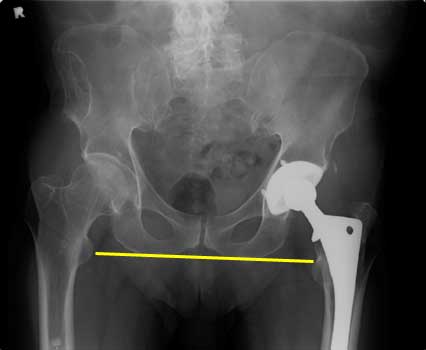

Leg Length Discrepancy

Transischial line is used to compare right and left greater and lesser trochanter positions. They should be at the same levels bilaterally.

In this case the right leg is 1 cm shorter than the left.